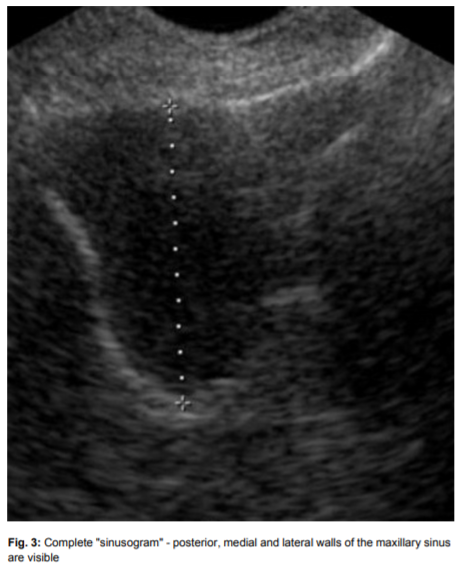

부비동의 뒷쪽, 안쪽, 바깥쪽 벽의 경계선이 보입니다.

부비동염 (축농증)에서는

부비동의 경계선이 보일 수 있고

점막의 비대나

새까맣게 물이 찬 것이 보입니다.

초음파 빔이 흩어지지 않고

내부 조직에 반사되어

영상이 나타납니다.